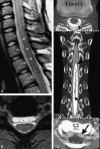

Despite extensive imaging, a source of bleeding is often not evident during the evaluation of patients with superficial siderosis (SS) of the central nervous system. An intraspinal fluid-filled collection of variable dimensions is frequently seen on spine MR imaging in patients with idiopathic SS. A similar finding has also been reported in patients with craniospinal hypotension. This review discusses the role of multitechnique imaging in the work-up of patients with SS and focuses on recent developments.